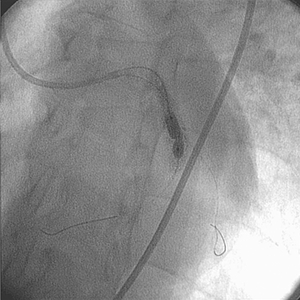

The medical team decided to use the Rotablator System. A 1.75 mm burr was passed through the lesion without difficulty over the RotaWire™ Floppy Guide Wire.

• Following the use of the Rotablator System, the lesion was post dilated with a 4.0 mm × 20 mm PTCA balloon catheter

• The use of the Rotablator System facilitated the delivery and expansion of a 4.0 mm × 9.0 mm stent with good angiographic appearance